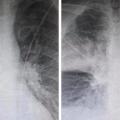

Σοκ προκαλούν οι δύο ακτινογραφίες που ανάρτησε στο Facebook ακτινολόγος από το ΚΑΤ, καθώς αποδεικνύουν την επίδραση που...